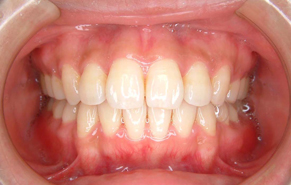

上下前歯のガタガタの症例です。ガタガタしている所は歯ブラシがとどかないので、茶色く着色しています。重なっている所は虫歯になっていることが、ほとんどです。

ガタガタの量が多く、物理的に顎の骨に入りきらないため、上下左右の前から4番目の歯(第一小臼歯)を抜いて、治療しました。抜かずに治療した場合、歯列の円周が広がり口元が突出してしまうため、抜歯をご選択されました。矯正後は歯磨きもし易く、歯の色も一緒にきれいになっています。